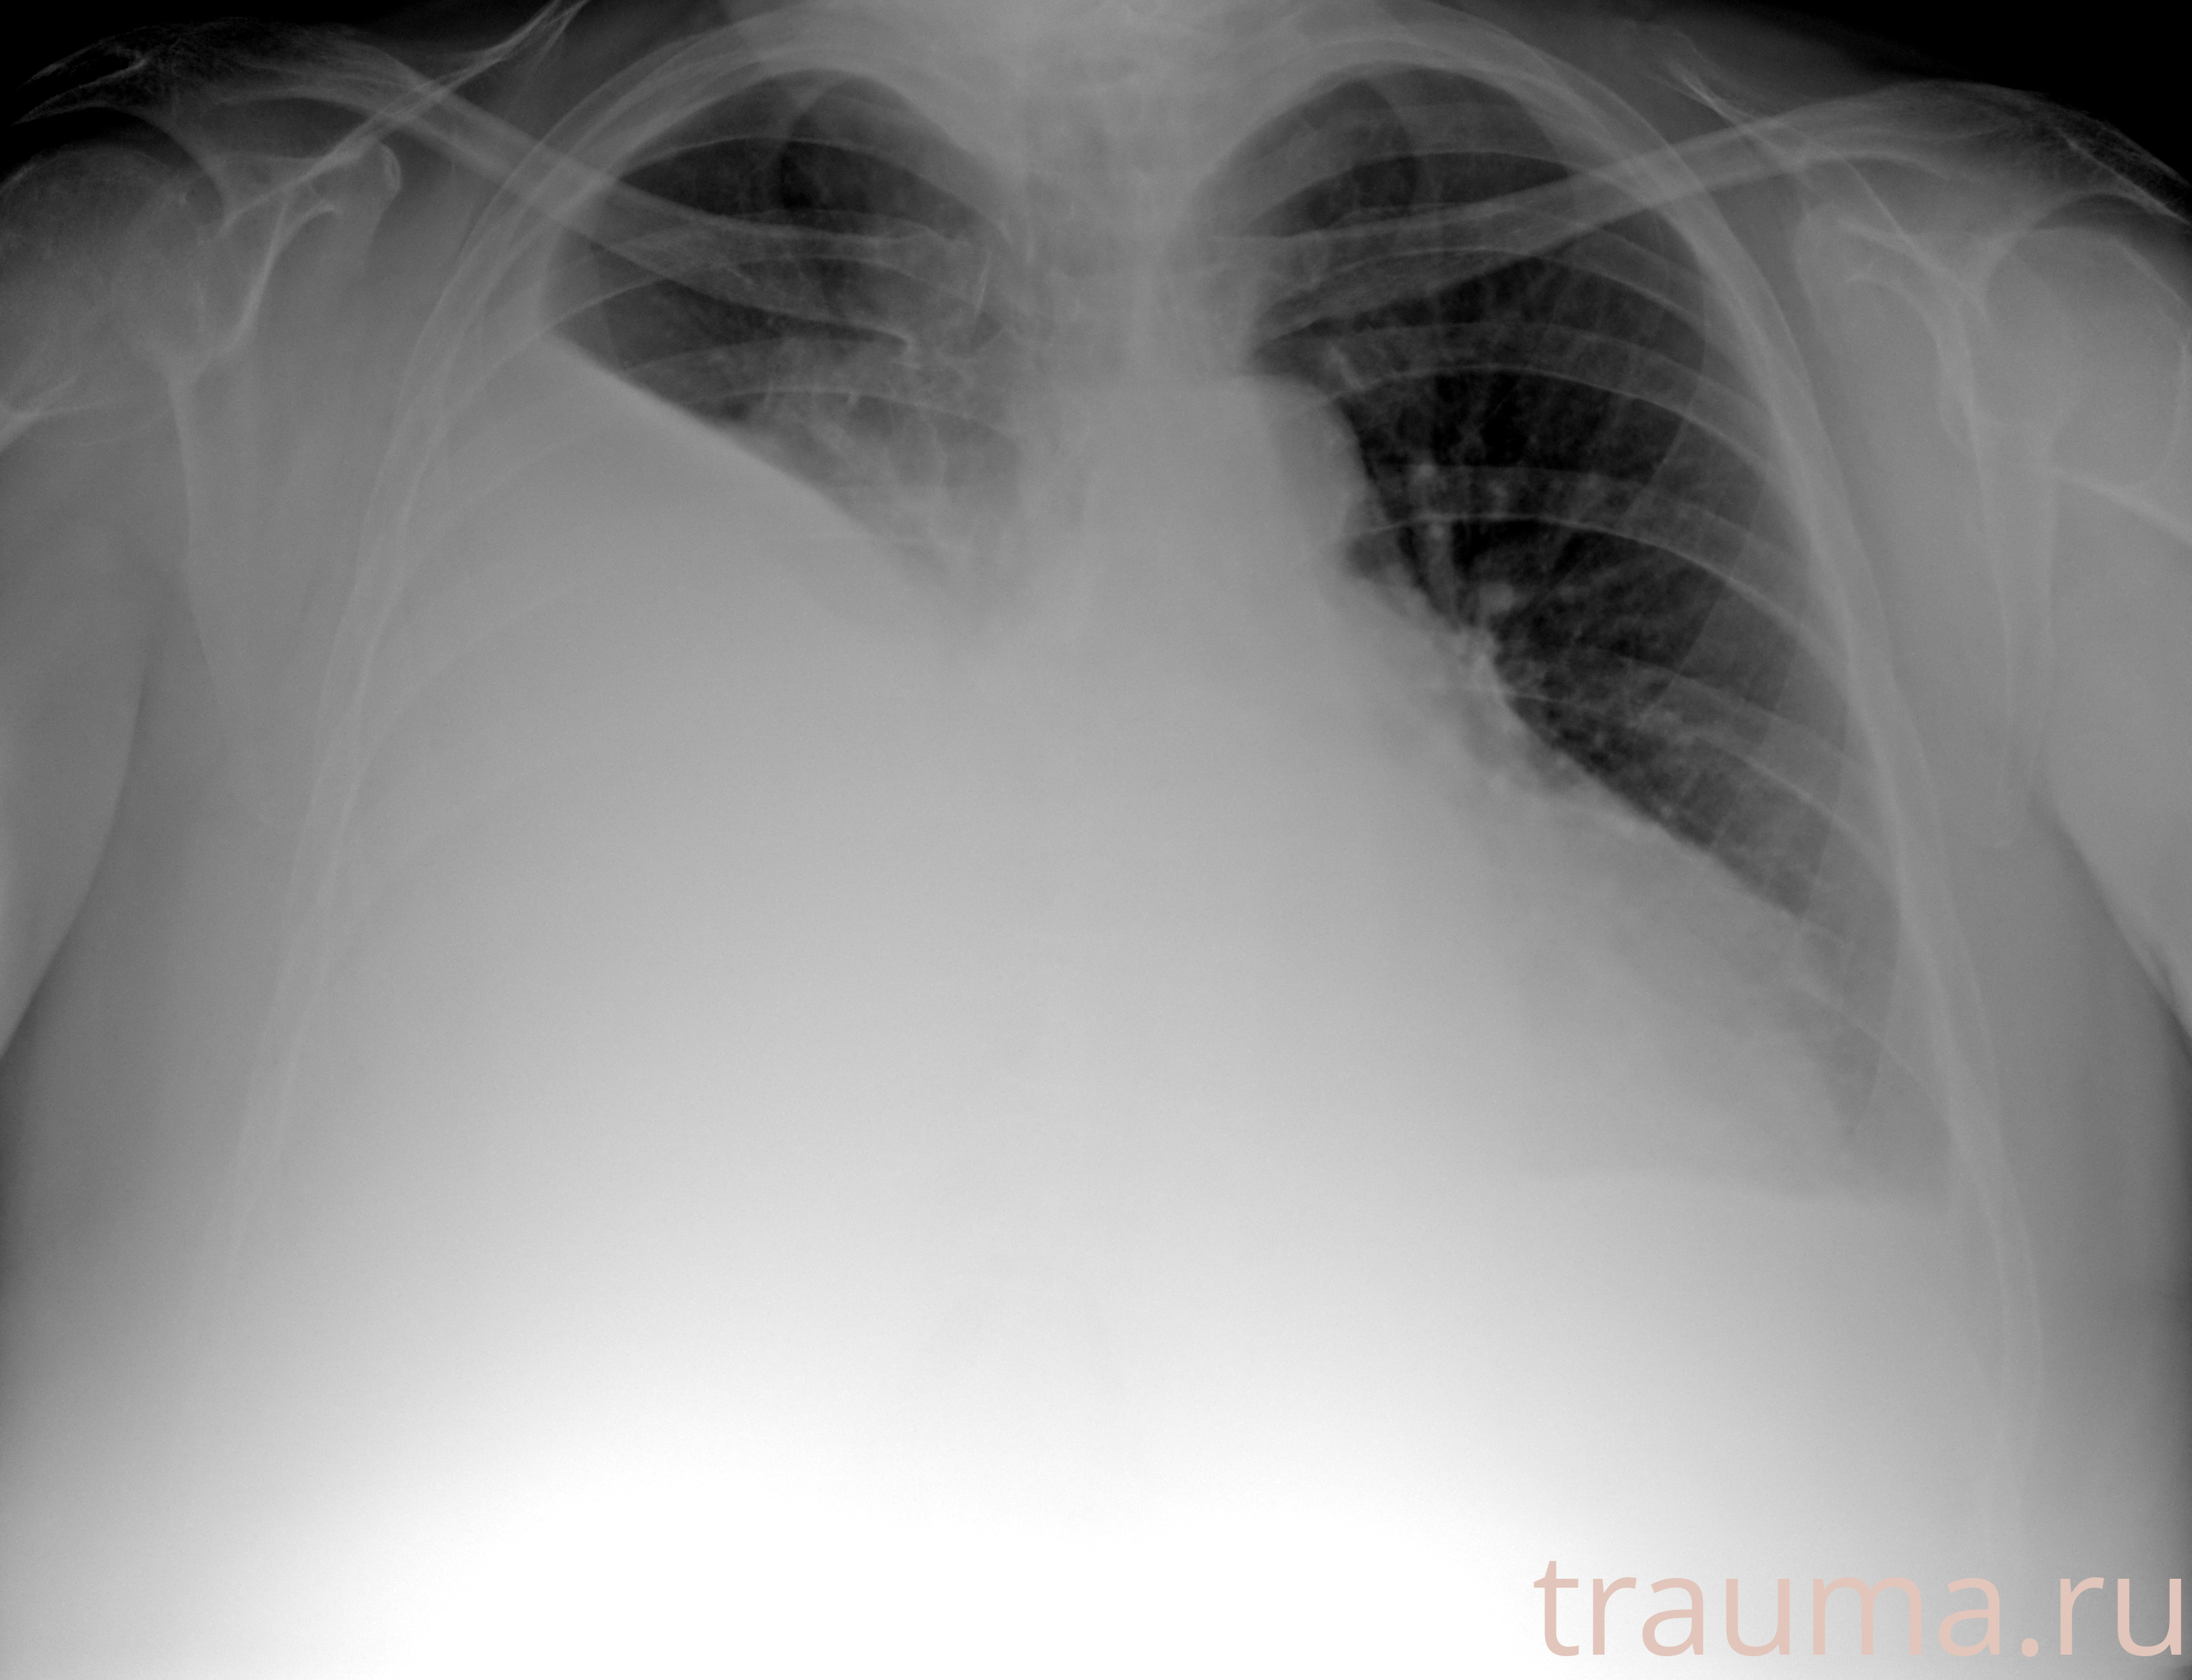

Рентген на дому: по вашему адресу приезжает врач-рентгенолог, травматолог-ортопед с мобильным рентгеновским аппаратом, проводит диагностику травмы или заболевания, делает необходимые рентгенограммы, дает рекомендации по дальнейшему лечению. Получить качественные снимки в домашних условиях возможно благодаря уникальной методике, разработанной МосРентген Центром для института  Склифосовского

при переломе шейки бедра и пневмонии от компании МосРентген Центр - партнера Института имени Склифосовского